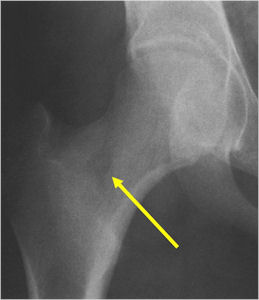

Sites:

- Femoral neck most common but can occur in any bone and any site within a bone (metaphyseal, diaphyseal, epiphyseal; cortical, medullary and periosteal)

- 50% occur in long bones of lower extremities

- Intracapsular osteoid osteomas are difficult to identify because there is no periosteum in the intracapsular region and hence a periosteal reaction does not occur.